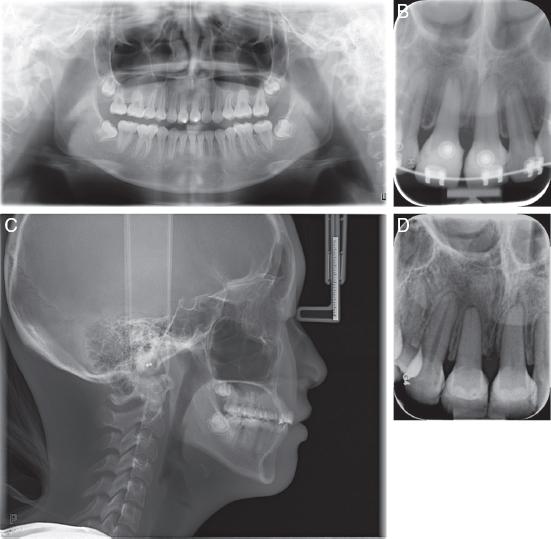

Figure 4.